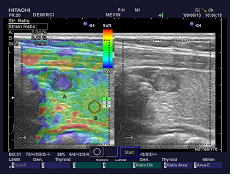

Bulgular: Fizik muayenede ağız boşluğu doğal gorunumdeydi. Boyunda palpasyonla ağrı ve hassasiyet mevcuttu. Tetkiklerde hipertiroidi saptandı. Servikal grafide yeni gelişen trakeal darlık ,tiroid ultrasonografide kanlama artmış, parankimde tiroidit saptandı.Hastaya oral Metilprednizolon Sodyum Suksinat, non-steroidal anti-inflamatuar ve betablokor tedavisi veridli. Hastanın şikayetleri tedavi altında geriledi. Tum bu bulgular ele alındığında hastada on planda radyasyon tiroiditi duşunuldu.